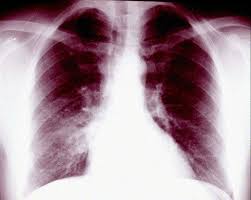

If you do have signs and symptoms, they may include: However, some residual scarring or damage may occur. Weak breathing (respiratory) muscles due to muscular dystrophy, spinal cord injury or another neuromuscular condition 8. Mucus plugs are also common in children, people with cystic fibrosis and during severe asthma attacks. Atelectasis, the collapse of part or all of a lung, is caused by a blockage of the air passages (bronchus or bronchioles) or by pressure on the lung. risk factors for atelectasis include anesthesia, prolonged bed rest with few changes in position, shallow breathing and underlying lung disease.